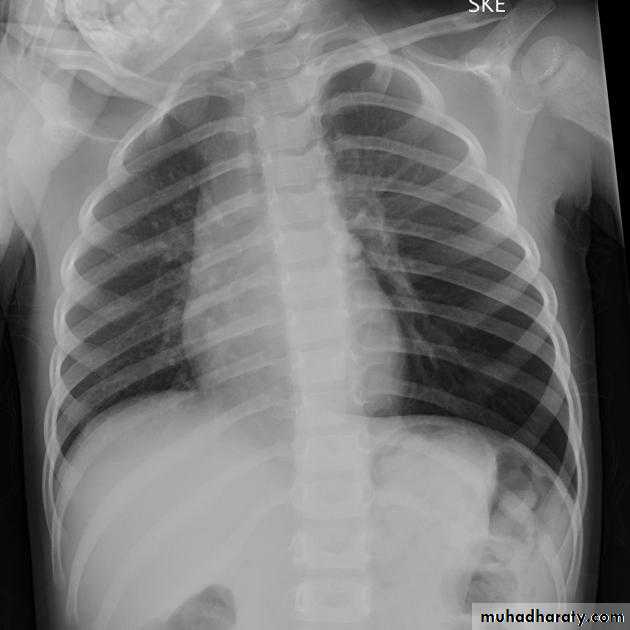

Unilateral obstructive emphysemaunilateral emphysema or atelectasis are the most common findings; only uncommonly will a radio-opaque foreign body be demonstrated ,Aspirated foreign bodies have a predominance for the right tracheo bronchial tree.